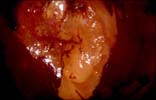

La transformation atypique de Grade II débutante va se traduire au niveau de la jonction par une acidophilie plus intense, la présence de nombreux orifices de glandes et une différence de tonalité au lugol par l’apparition d’un aspect jaune foncé.

Au lugol, la limite entre ces deux processus de TAG 1 et de TAG 2 est soulignée par une différence de tonalité :